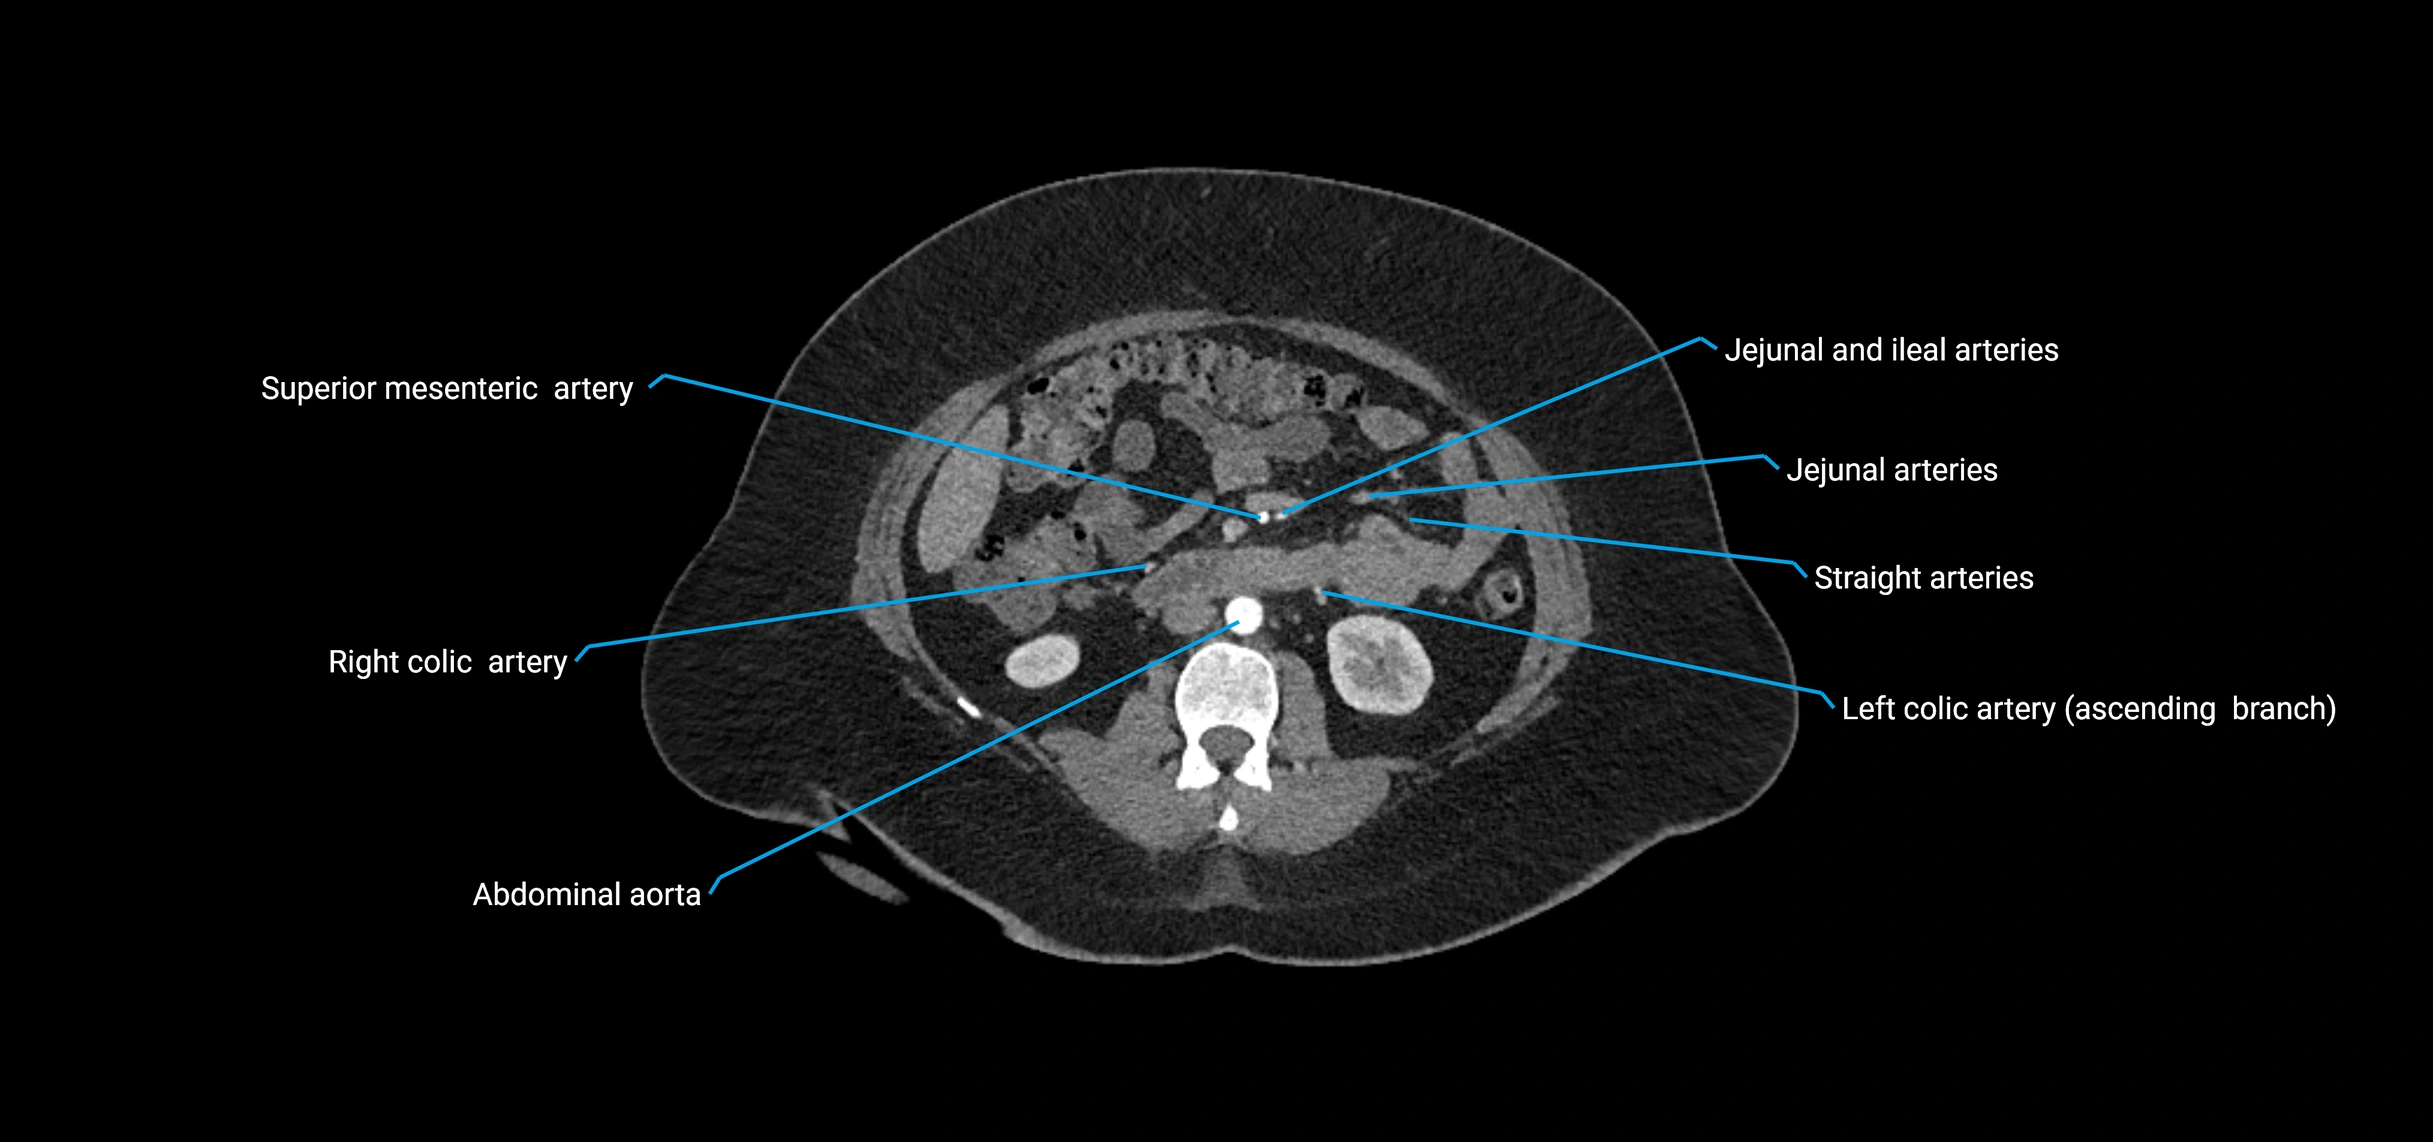

Contrast-enhanced CT (CTA):

• Gold standard for abdominal aortic imaging

• Provides excellent detail of lumen, wall, aneurysm, thrombus, and branch vessels

• Multiplanar and 3D reconstructions help in aneurysm measurement, stent graft planning, and dissection evaluation